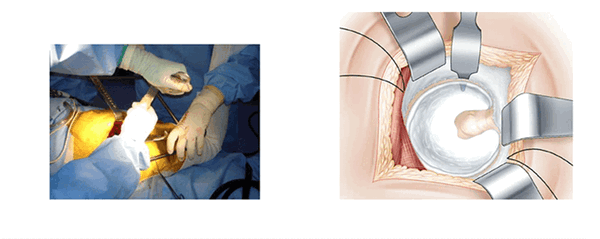

Рис.2 Мини-инвазивный метод с задне-боковым доступом.

Заднебоковой доступ в настоящее время все шире применяется при малоинвазивном эндопротезировании тазобедренного сустава. Исторически так сложилось, что риск первичного вывиха при заднебоковом доступе случается чаще, чем при применении переднего или бокового доступа. Техника выполнения малоинвазивного метода с применением заднего доступа направлена на минимальное повреждение мышц и суставной сумки.

Сохранение мышц неповрежденными, или, по крайней мере, малоповрежденными, снижает риск вывиха протеза и ускоряет процесс реабилитации и восстановления двигательной функции конечности. Приводимое описание хода операции направлено на выявление трудностей, связанных с малым разрезом и сохранением мышц и связок. Особое внимание уделено четырем позициям, которые позволяют поочередно напрягать и расслаблять мягкие ткани и минимизировать вмешательство.